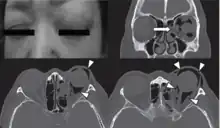

| Woman with preorbital swelling in orbital emphysema shown in CT scans | |

Computed tomography (CT)

Computed tomography is effective and sensitive in the diagnosis of orbital emphysema,[3][37] as it can confirm the anatomical location and size of air, bony defects, indentation of the eyeball, and the condition of the optic nerve, as well as the presence of any extraocular muscle entrapment and herniation of preorbital fat into the sinus cavities.[3][15][38] The location of the orbital emphysema is present near the site of the fracture.[1][3] The scans are usually taken along the transverse plane. Transverse images allow the evaluation of fractures in medial and lateral orbital walls. By reformatting these transverse images or taking coronal images, the examination of orbital floor and roof is permitted. Helical scanning is preferred as it has a lower imaging time and radiation dose comparing to conventional scanning, especially when reforming transverse helical scans into coronal images.[3] The staging of orbital emphysema can then be determined with visual acuity examination and ophthalmoscopy.[6] A disadvantage of using a CT scan is that when detecting air after orbital trauma, the presence of a wooden foreign object can give a false positive result of orbital emphysema. The wooden object can mimic the presence of orbital emphysema. Therefore, patients’ medical history is crucial in making the correct diagnosis.[3]